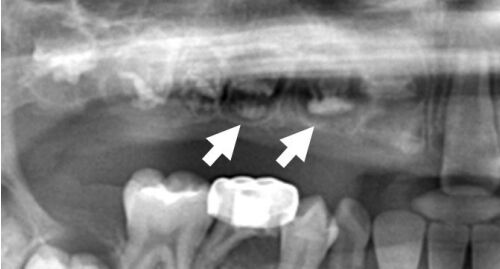

70.依據附圖X光片,最不可能的診斷為何?(A)osteoporosis(B)osteomyelitis(C)osteoradionecrosis(D)medication-related osteonecrosis(MRONJ)